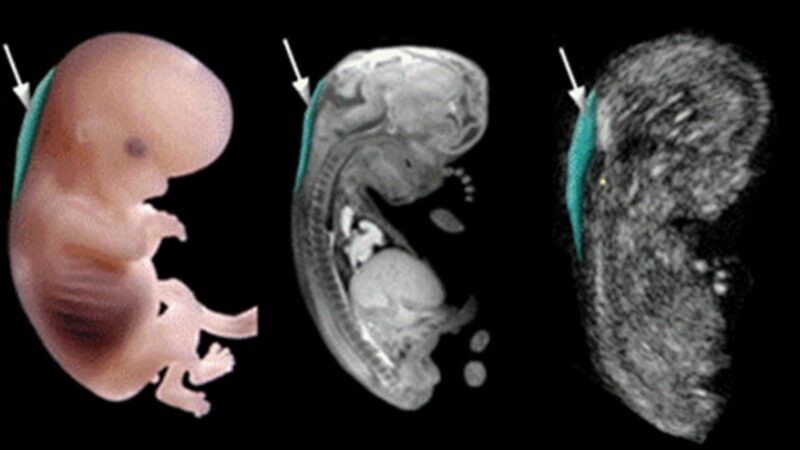

Tuần thứ 11 của thai kỳ (tương đương tuần thứ 9 sau thụ tinh) nằm trong ba tháng đầu tiên của thai kỳ, và đây là thời điểm em bé chính thức được miêu tả bằng từ "thai". Thai nhi 11 tuần tuổi phát triển rất nhanh, ngoại hình đã có hình dạng đặc trưng của loài người.

Đầu thai nhi có độ dài bằng khoảng một nửa tổng chiều dài của thai nhi, phần thân bắt đầu phát triển nhanh chóng. Khuôn mặt của thai nhi rộng ra, hai mắt tách xa nhau, mí mắt nhắm lại. Tai đã gần đạt được hình dạng cuối cùng, mũi đã xuất hiện đường khí đạo, trong miệng đã hình thành lưỡi và hàm ếch, mầm răng tương lai xuất hiện. Núm vú có thể nhìn thấy được. Tay và chân ở phía trước của cơ thể, không còn hình dạng mái chèo nữa, mà các ngón tay và ngón chân đã xuất hiện. Hồng cầu bắt đầu hình thành trong gan thai nhi. Đến cuối tuần thứ 11, bộ phận sinh dục ngoài bắt đầu phát triển.

Để phát hiện sớm hội chứng Down ở thai nhi, bác sĩ có thể siêu âm đo độ mờ da gáy của thai nhi vào tuần thứ 11 thai kỳ. Độ mờ da gáy được xác định chính xác nhất trong khoảng thời gian từ tuần 11 đến tuần 13 tuần 6 ngày. Nếu tiến hành siêu âm quá sớm, kết quả sẽ không chính xác vì lúc này thai nhi còn quá nhỏ. Còn nếu quá muộn, thì kết quả cũng sẽ không còn ý nghĩa.